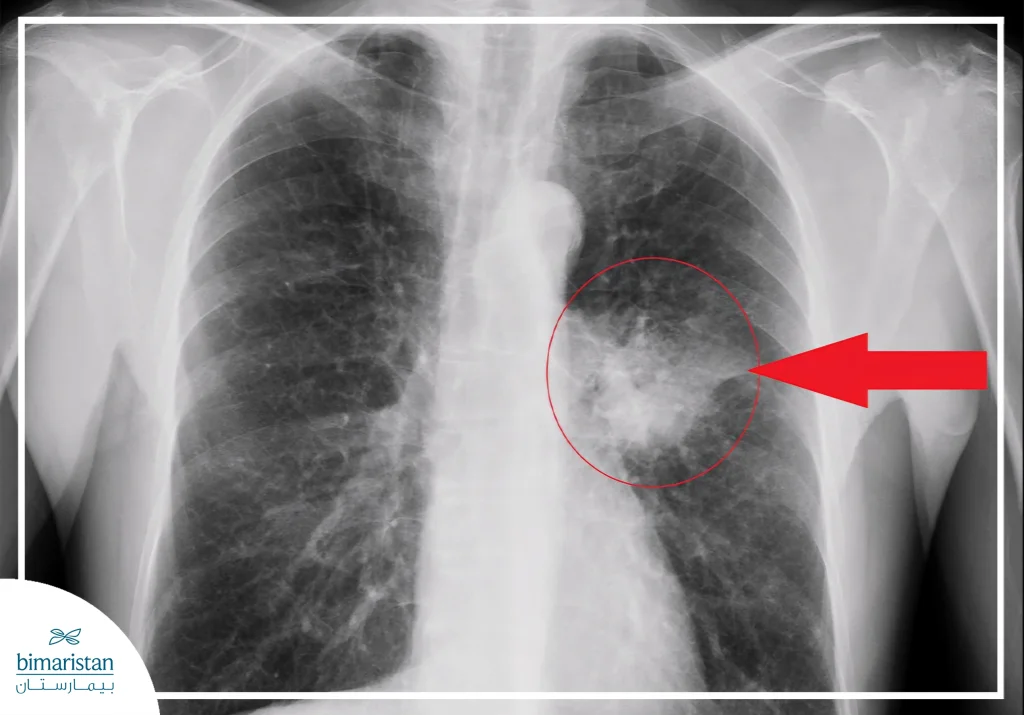

يُكتشف سرطان الرئة الغدي في كثير من الحالات صدفةً أثناء إجراء فحص شعاعي للصدر لأسباب غير مرتبطة بالسرطان، إذ قد يظهر على صورة الأشعة ظلّ غير واضح أو منطقة غير طبيعية في نسيج الرئة، ورغم أنّ التصوير الشعاعي يُعد وسيلة مبدئية مفيدة، إلا أنّ نحو ربع حالات سرطان الرئة قد لا تُكشف بالأشعة السينية وحدها، مما يستدعي إجراء فحوص أكثر دقة لتأكيد التشخيص.

- الأشعة السينية للصدر: تُستخدم كاختبار مبدئي لكنها قد لا تُظهر الأورام الصغيرة أو الطرفية.